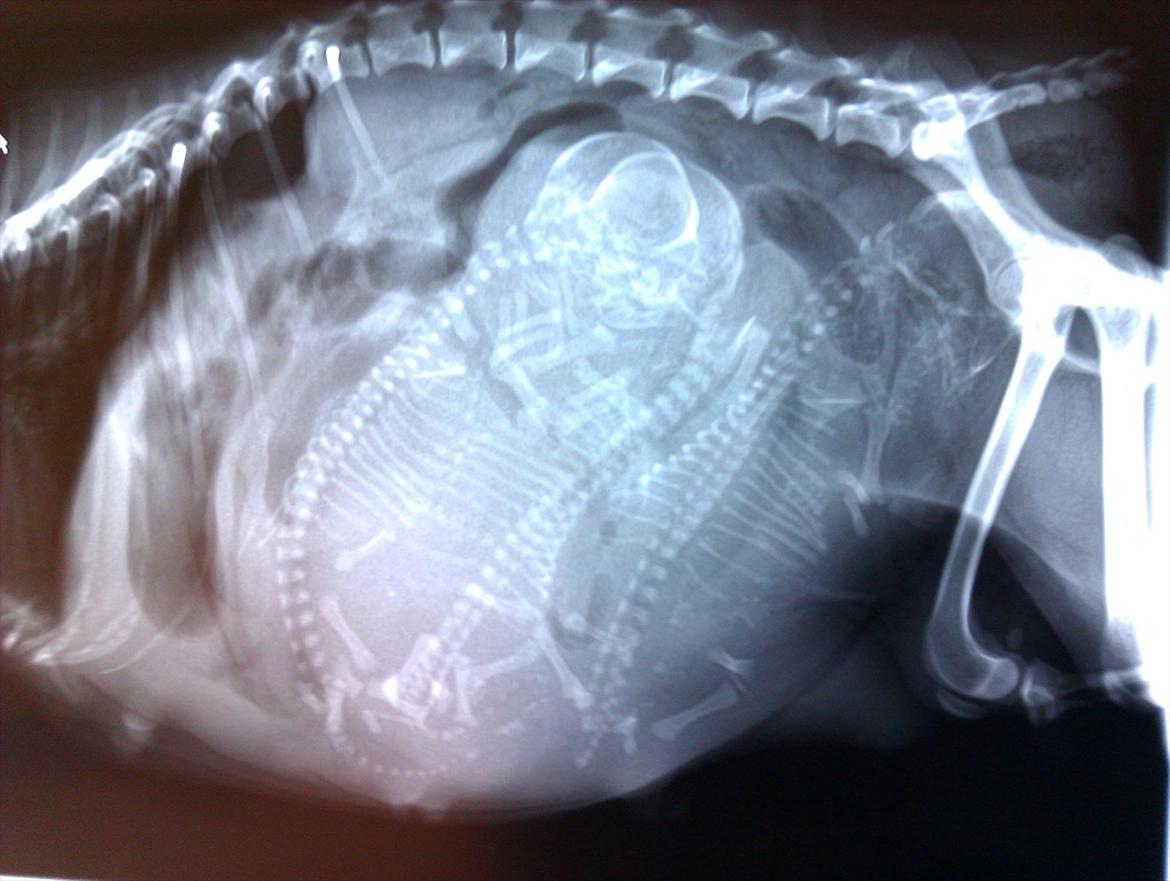

Blanding af racer chevy - scanning's billeder.. billede 3